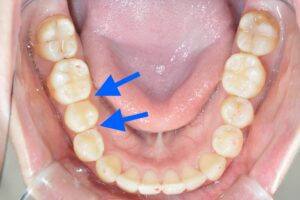

具体的にどこが気になるかというと

・上の前歯が少し傾いている

・右上2番目の歯をもう少し前に出したい

・下顎に隙間があり物が挟まる

以上3点の改善と噛み合わせの調整のため、2回目の追加治療を行うこととなりました。